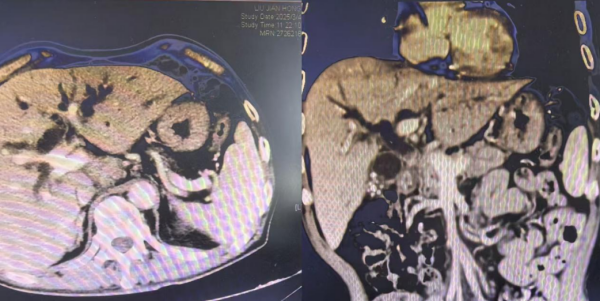

患者胆总管受压,肝内胆管重度扩张

67岁的患者高先建(化名),诊断结果为肝门部转移瘤合并恶性梗阻性黄疸,高胆红素血症。全身皮肤及巩膜明显黄染,厌食厌油、精神差、嗜睡、尿黄。在接受护肝、退黄等药物治疗10余天后,效果欠佳。

李岳勇分析,患者发生阻塞性黄疸,肝脏功能受损,代谢能力下降,大量的胆红素积聚在肝脏,进一步加剧了肝脏的损伤,同时还会加重肾脏负担,引起肾功能衰竭,甚至会对大脑和神经产生不可逆性损害。

所以,首先要解除胆道梗阻这个难题。一般的处理方案就是外科手术治疗,但患者处于恶性肿瘤终末期,同时合并糖尿病、高血压等多种慢性基础疾病,身体状态差,传统外科手术风险高、患者耐受性差。